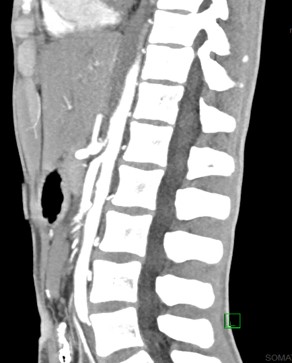

Abdominal computed tomography angiography during hospitalization

FINDINGS (abbreviated): Normal robust enhancement of abdominal aorta, origins of celiac, superior mesenteric and renal arteries are demonstrated. The aortomesenteric angle measures 14 degrees. The aortomesenteric distance at the level of the duodenal crossing is 6 mm.

IMPRESSION:

- Interval resolution of previously demonstrated marked distention of the stomach. Proximal duodenum is mildly dilated, but significantly improved compared to prior.

- Both the aortomesenteric angle and aortomesenteric distance are decreased, as may be seen with SMA syndrome. Clinical correlation and follow-up care are recommended.

- Left chest tube is present with small left pneumothorax.

- Subcutaneous air is present with soft tissues in the lower chest.

- Small amount of posterior pneumomediastinum is present.

- Mild splenomegaly is present. The spleen appears elongated and relatively thin transversely.